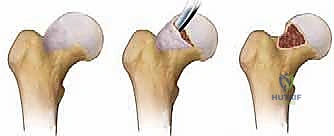

التحدي الأكبر: الحفاظ على التروية الدموية (The Blood Supply)

التحدي المرعب تاريخياً في خلع مفصل الورك كان خطر الإصابة بـ النخر اللاوعائي (Avascular Necrosis - AVN)، وهو موت رأس الفخذ بسبب انقطاع الدم عنه. العبقرية في تقنية "غانز" التي يتقنها الدكتور هطيف تكمن في القدرة على خلع رأس الفخذ بالكامل من مكانه مع الحفاظ التام على الأوعية الدموية المغذية (الشريان المنعطف الفخذي الإنسي - Medial Circumflex Femoral Artery). يتم ذلك من خلال نهج جراحي دقيق للغاية يحمي العضلات والأوعية.